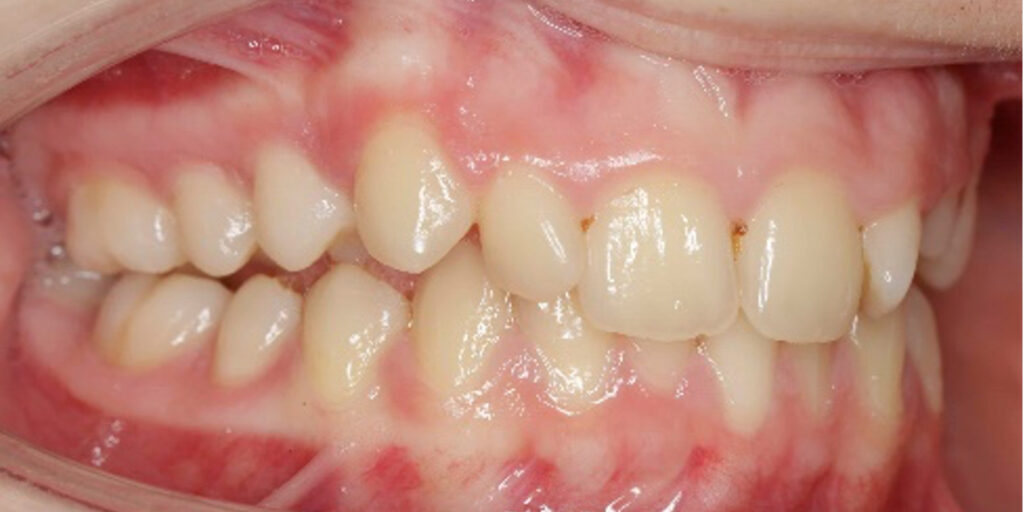

The 14-year-old female patient visited the orthodontic practice in February 2021. The chief complaint was that her upper arch was affecting her confidence in her smile. Upon examination, the patient was found to have a normodivergent facial pattern and a skeletal class II with mandibular retrusion. An intraoral examination revealed narrow arches, a class II molar and canine relationship, deep bite, retroclined upper and lower incisors, and retained teeth 63, 74, and 84.

After undergoing maxillary expansion, Dr. Sorina Blaj assessed the patient again in September 2021, and at that point, tooth 84 had exfoliated, tooth 44 had erupted, and tooth 23 had started to erupt.

After considering that 23 no longer needed to be surgically exposed, Dr. Blaj, the patient, and her parents decided to use Spark Clear Aligners to correct dental issues. The treatment began in November 2021, utilizing the 3D Approver Software™ to design a digital plan. The plan aims to:

The treatment includes sequential distalization of the maxillary teeth and mesialization of 3.6, virtual extraction of 74, composite attachments on all distalizing teeth, class II elastics, bite ramps on upper central incisors, IPR and eruption guides for teeth 23 and 35.